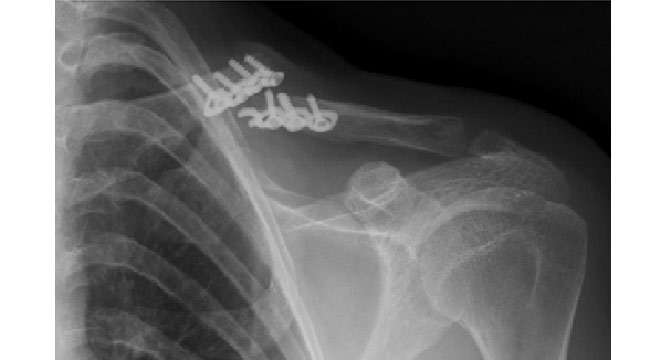

خارج کردن پیچ ۷ سانتیمتری از معده کودک ۱۰ ساله

ندای استان:با تلاش تیم مجرب پزشکی و به همت تیم تخصصی آندوسکوپی بیمارستان شهدای خلیجفارس بوشهر، پیچ ۷ سانتیمتری از معده کودک ۱۰ ساله خارج شد.